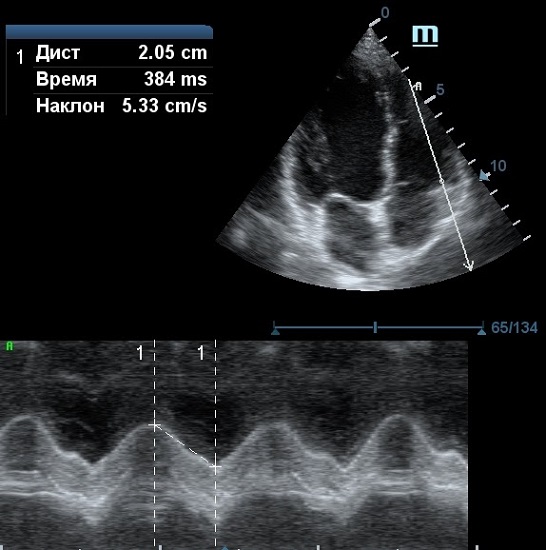

TAPSE - показатель амплитуды движения латеральной части кольца трикуспидального клапана, позволяет количественно и быстро оценить систолическую функцию правого желудочка, норма которого составляет более 17 мм. Главным условием является проведение линии М-режима параллельно стенке правого желудочка в апикальном четырех камерном сечении, что легко достигается при Free Xros.

MAPSE - амплитуда движения латерального кольца митрального клапана, позволяет рассчитать фракцию выброса по формуле EF = 4.8 × MAPSE (mm) + 5.8, очень быстрый и гораздо более точный («прародитель Strain») метод чем широко распространенный метод Teicholtz. В современных приборах можно легко добавить свою формулу при отсутствии ее в стандартном калькуляторе. Главным условием является проведение линии М-режима параллельно стенке левого желудочка в апикальном четырехкамерном сечении, что легко достигается при использовании функции Free Xros.